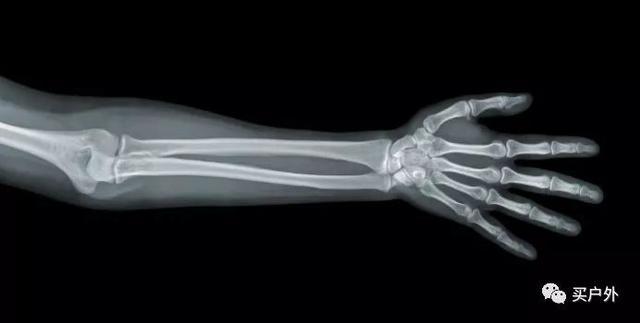

下圖,膽小者可忽略:

上圖銷魂的“姿勢”大概就是我們平常握杖的姿勢。人體所有的關節都有一個基本特點:容易受傷,不耐疲勞。 腕關節更是人體關節里格外弱小的那個。(如果你用鍵盤姿勢不正確,不用多久就會出現腕關節疲勞甚至損傷,何況重裝遠征...)